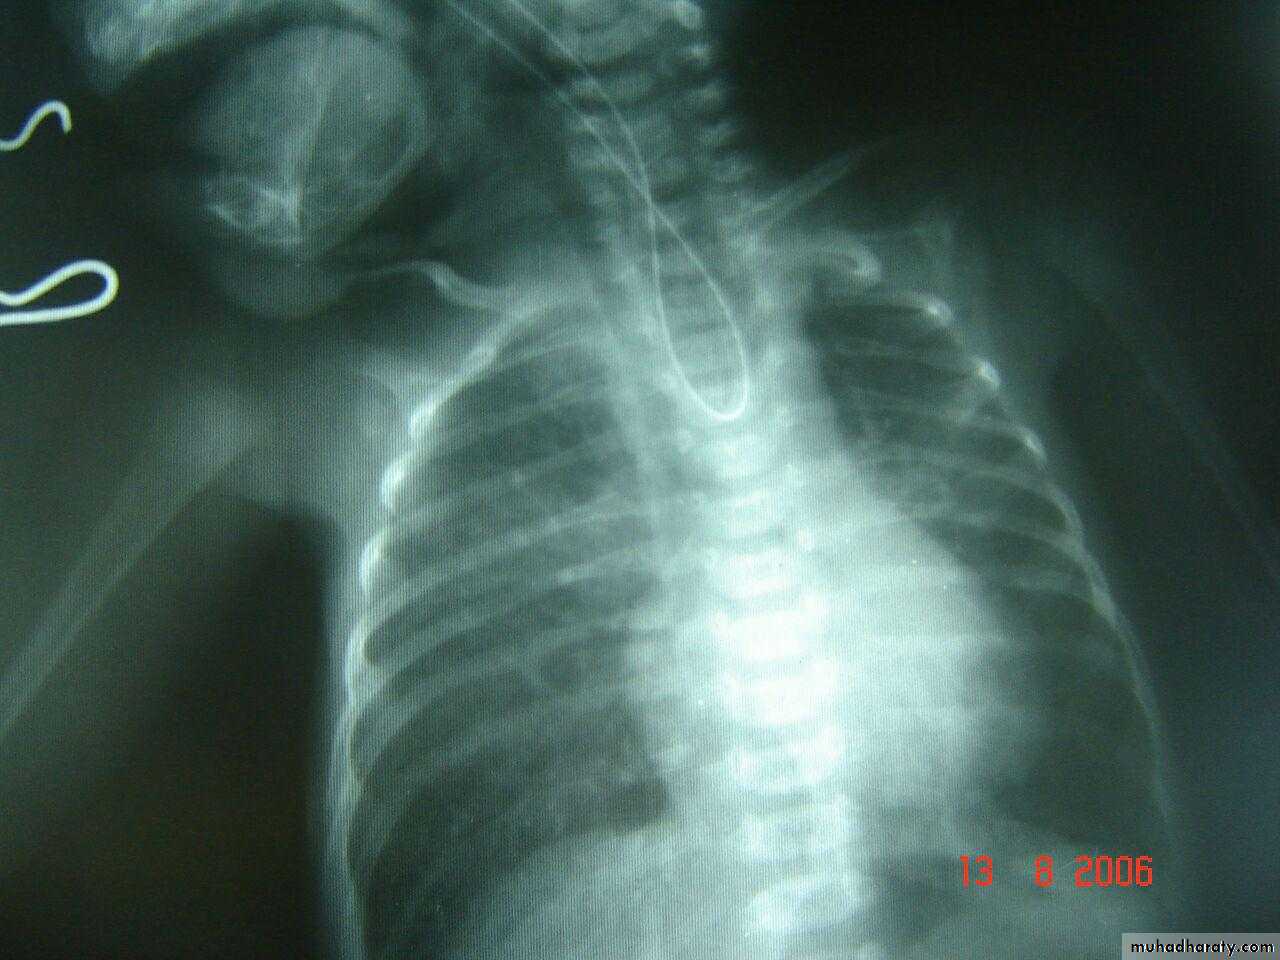

pneumothorax

Tention pneumothorax ( shifting mediastinum )

Endotracheal tubeSo, +ve pressure ventilation complicated to pneumothorax

Rt. Total lung collapse

RDS with pneumomediastinum as rds complication